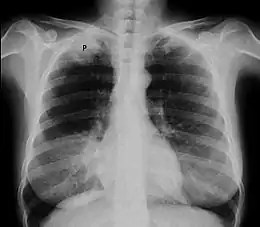

- Radiographie thoracique montrant une opacité de l'apex[1]